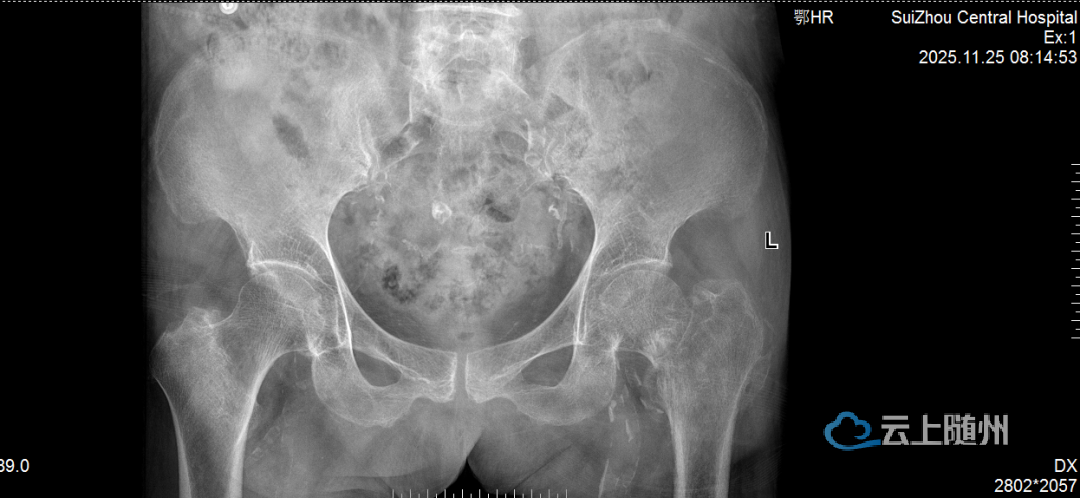

术前术后